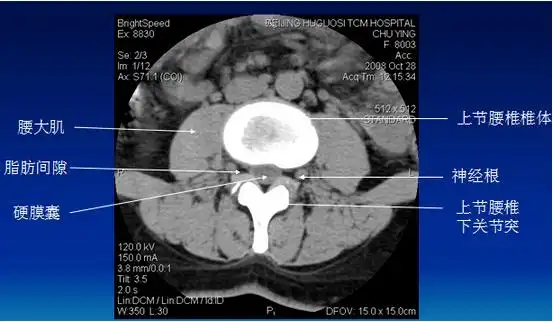

腰椎 #腰椎间盘突出 #腰间盘突出 #腰椎间盘突出症 #坐骨神经痛

腰间盘突出诊断分析

腰椎间盘突出ct诊断

腰椎间盘突出的影像诊断